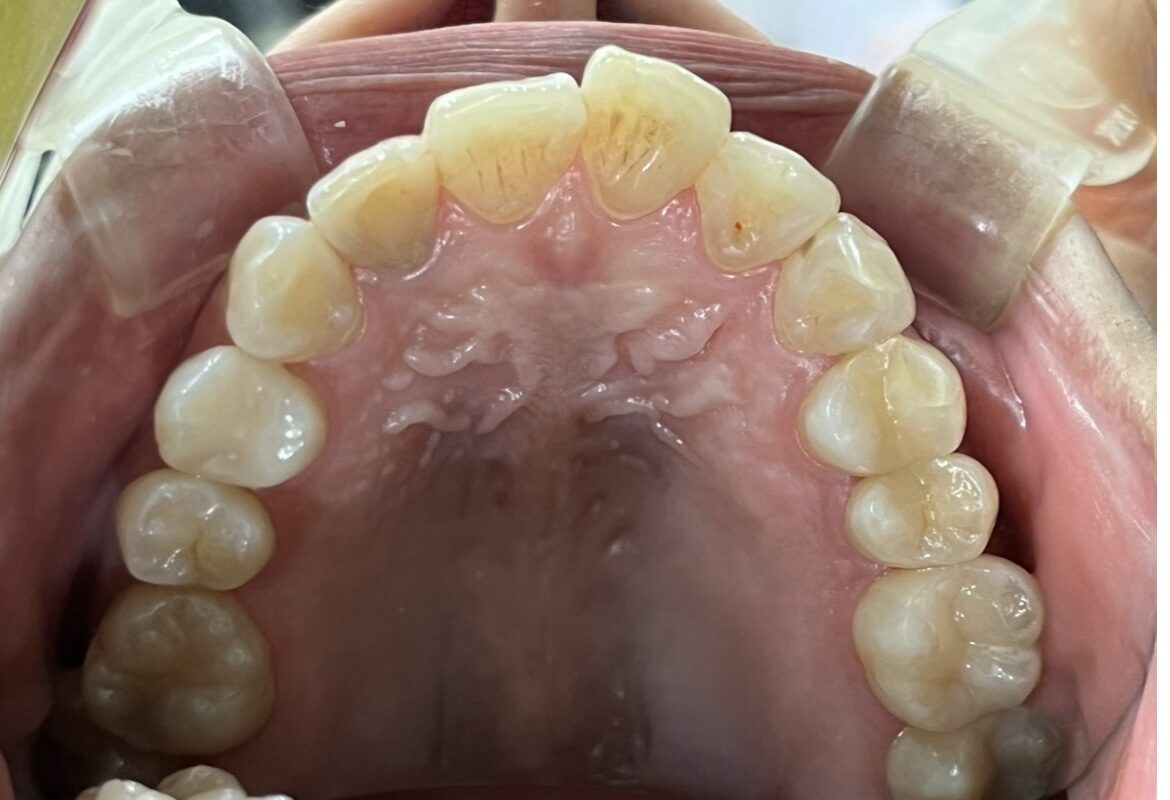

叢生の症例1(表側矯正)

| 年齢 | 10代男性 |

| 主訴 | 前歯のガタガタ |

| 診断 | 叢生 |

| 治療方法 | 上下・表側ワイヤー矯正(今回抜歯はしていません) |

| 治療期間 | 11か月 |

| 費用 | 1,050,500円(税込) |

| リスク・副作用 | 痛み/歯根吸収/歯肉退縮/後戻り など |

本症例では歯が重なっている叢生と、前から見ると曲がっている状態でした。

歯列のスペースを確保しながら歯並びを整えるため、

表側矯正を用いて治療を行いました。

治療後は歯並びとかみ合わせが改善し、

見た目だけでなく歯磨きもしやすい状態になりました。

※虫歯の治療は矯正治療後に仕上げています。

※正中を合わせるには抜歯等が必要になる場合があります。